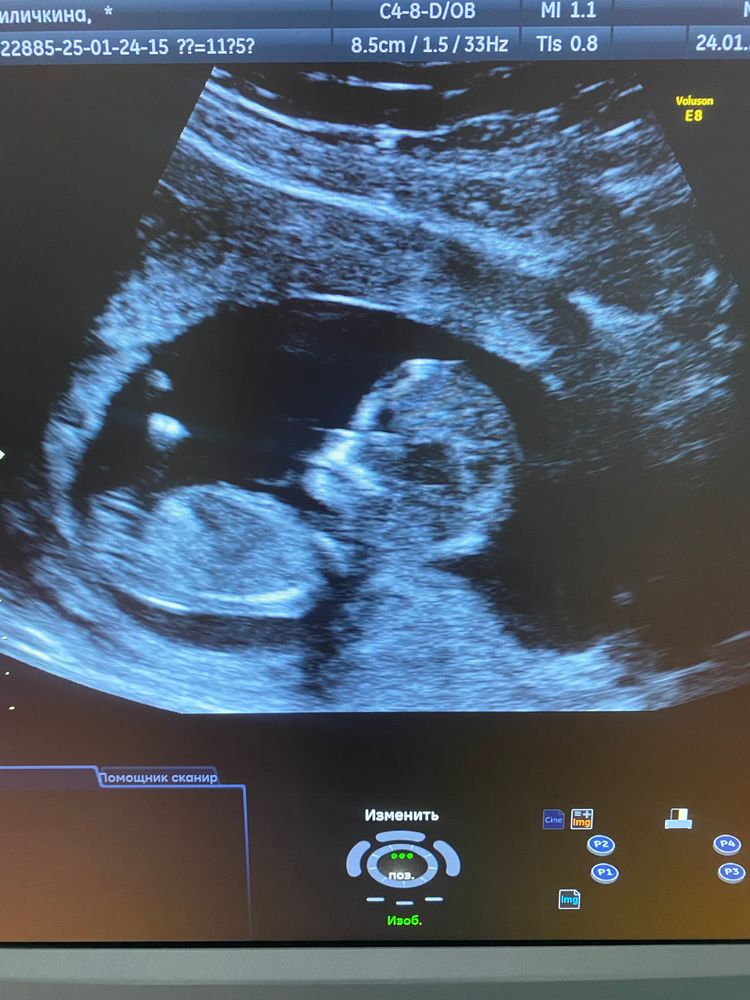

12 неделек, скрининг пройден

мама дважды, ой, сказали не очень видно, но будто больше на девочку похоже. Я очень надеюсь))

30.01.2025